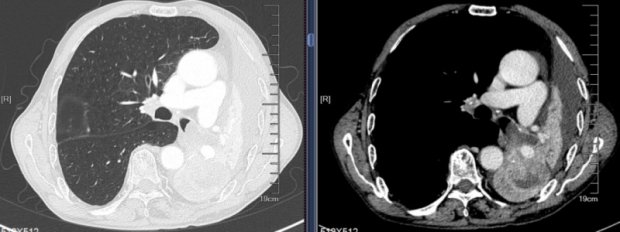

医疗动态 | 命悬一线!徐州一院呼吸专家镜下治疗解除狭窄,畅通患者呼吸之道

近日,饱受憋喘症状所折磨的杜女士来到徐州一院呼吸与危重症医学科就诊。三病区主任崔文洁了解发现杜女士既往有甲状腺恶性肿瘤病史,现出现多部位脏器及淋巴结转移,近期胸部...